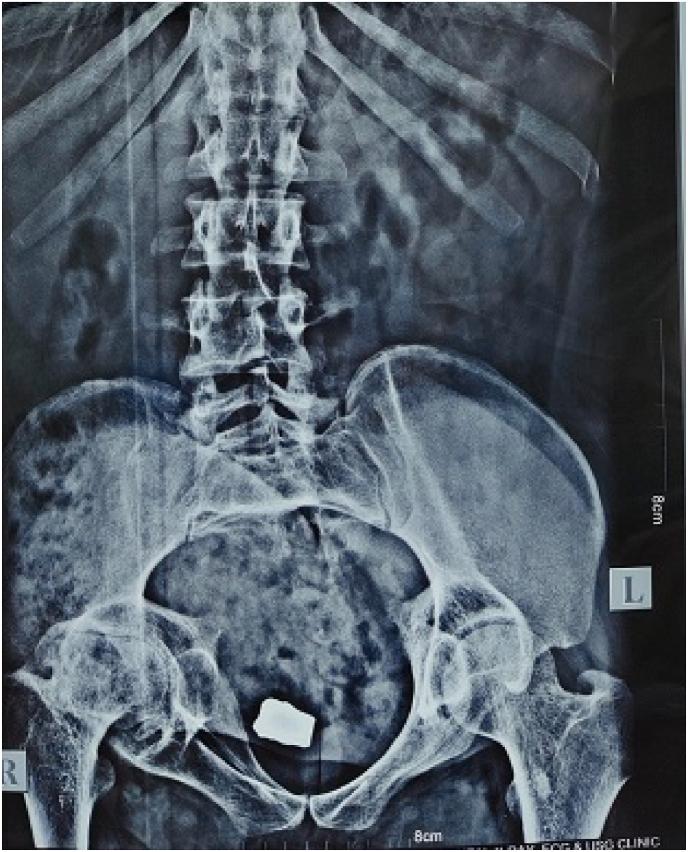

Secondary bladder stones in young adults are usually a result of bladder outlet obstruction secondary to urethral stricture disease or neurogenic bladder. Foreign body inside bladder is a perfect nidus for the development of secondary bladder stone. We report a rare case of bladder stone in a young adult developing on the retained blast fragment inside bladder.

年轻成年人的继发性膀胱结石通常是尿道狭窄疾病或神经源性膀胱继发膀胱出口梗阻的结果。膀胱内的异物是继发性膀胱结石形成的理想病灶。我们报告一例罕见的年轻成年人膀胱结石病例,其结石由膀胱内残留的爆炸碎片形成。